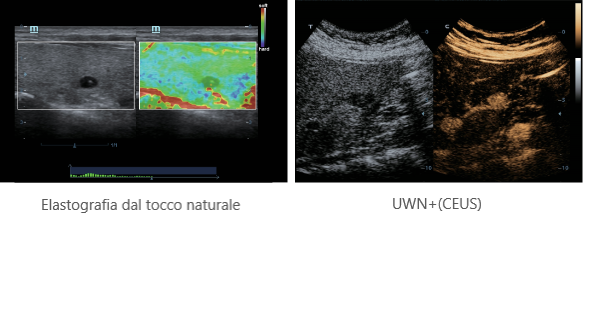

X-Insight ├© una soluzione completa studiata per offrire la migliore qualit├Ā diagnostica.

La nuova soluzione di Mindray ├© la traduzione pratica delle esigenze quotidiane dei clienti in soluzioni cliniche, il tutto con tecnologie ad ultrasuoni all'avanguardia ed in continua evoluzione.

Proponendosi come partner affidabile, DC-60 Exp con X-Insight si concentra su ci├▓ che conta veramente, semplificando la gestione della pratica clinica quotidiana con facilit├Ā e sicurezza.

Progettato per rispondere al meglio alle esigenze del cliente, DC-60 Exp con X-Insight ├© studiato per offrire un'efficienza elevata nel campo dell'imaging di precisione, grazie a una chiarezza immediata (eXpress Clarity), allŌĆÖeccezionale intelligenza (eXceptional Intelligence), oltre a vantare una lunghissima esperienza (eXceeding Experience).